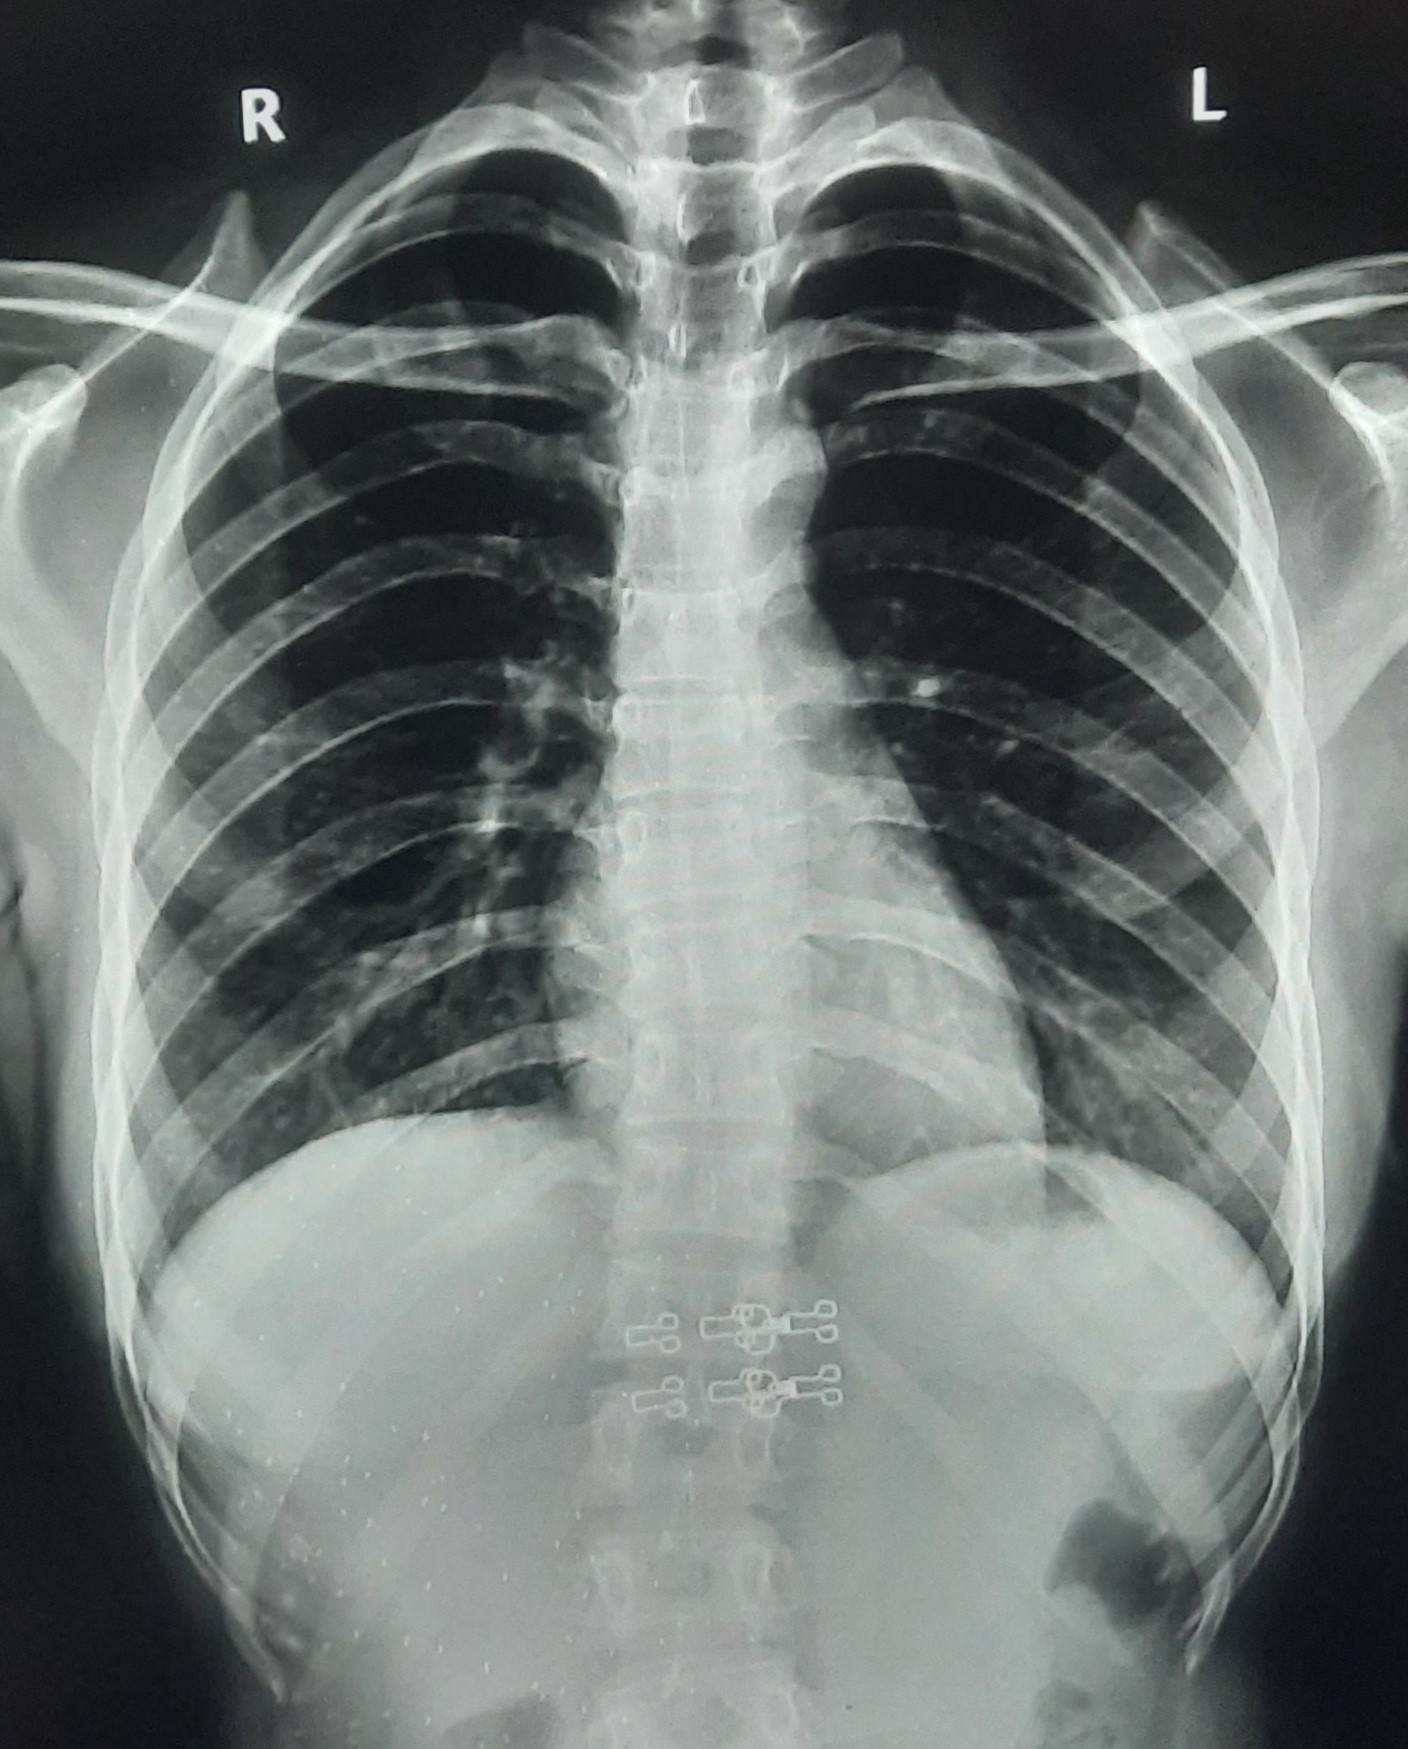

| 350 | IGGMC, Nagpur, Nagpur | P2 | 29-4122 | Pravin Thaware | Consent taken on Paper | 32 Yrs. |

Provisional Diag : Pre-Employment Medical fitness

Final Diag : CxR No Finding (Medical Fitness) |

Pure Normal Case (Cases with no complaint, NAD or medical fitness cases) | NODULAR OPACITIES SEEN IN BILATERAL HILAR REGION | No abnormality visible on x-ray |